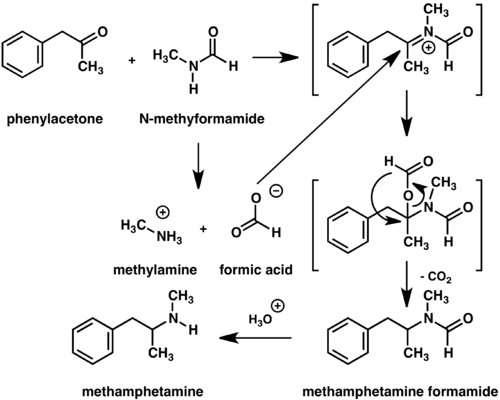

Racemic methamphetamine may be prepared starting from phenylacetone by either the Leuckart[157] or reductive amination methods.[158] In the Leuckart reaction, one equivalent of phenylacetone is reacted with two equivalents of N-methylformamide to produce the formyl amide of methamphetamine plus carbon dioxide and methylamine as side products.[158] In this reaction, an iminium cation is formed as an intermediate which is reduced by the second equivalent of N-methylformamide.[158] The intermediate formyl amide is then hydrolyzed under acidic aqueous conditions to yield methamphetamine as the final product.[158] Alternatively, phenylacetone can be reacted with methylamine under reducing conditions to yield methamphetamine.[158]